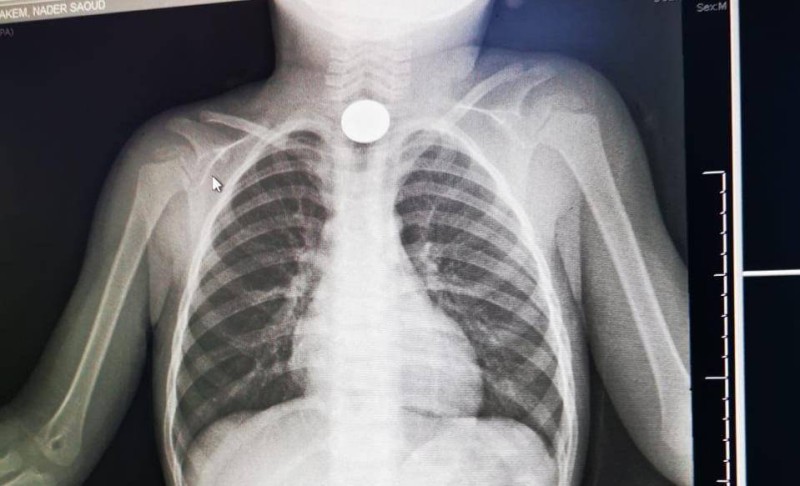

نجح فريق طبي متخصص بمستشفى القريات العام في استخراج جسم معدني في أعلى المريء لطفلة تبلغ من العمر 3 سنوات، تبين بعد إجراء التحاليل والأشعة اللازمة، ما استدعى اتخاذ قرار بالتدخل واستخراجه بواسطة المنظار.

وأوضحت صحة القريات أن الجسم عبارة عن «عملة معدنية» أعلى المريء، حيث تم استخراجه والطفلة حالياً بحالة صحية جيدة.